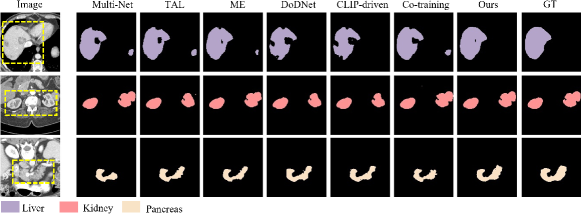

Tables I, II, III and IV present the segmentation results for the head and neck, chest, abdomen, and pelvis, respectively. Figs. 4, 5, 6 and 7 provide visualizations of these methods. The following conclusions can be drawn from these results:

Unified segmentation models generally outperform Multi-Net, as indicated by combined DSC and ASSD metrics. Among channel adjustment methods, ME outperforms TAL by leveraging non-overlapping organ annotations across datasets. The conditionally-guided DoDNet achieves sub-optimal results in the chest and abdomen but performs poorly in the head and neck and pelvis, particularly for the chiasm and parotid glands; The method also struggles to distinguish between symmetrical structures (e.g., parotid glands and humerus), as noted in COSST [4]. The CLIP-driven method performs poorly across all regions, especially for less frequent organs and structures like the chiasm. The Co-training method, based on two stage pseudo-labeling, achieves competitive results, particularly in the pelvis. Overall, our method outperforms others across all regions, especially for small organs like the chiasm and elongated organs like the esophagus. Visually, our method aligns more closely with GT, avoiding the segmentation errors of channel adjustment and the issues with symmetric structures in conditional guidance methods.

The effectiveness of our method has been demonstrated through the experiments on diverse datasets encompassing the head and neck, chest, abdomen, and pelvis, which has consistently achieved superior performance in each of these regions, surpassing the state-of-the-art methods (see Tables I, II, III and IV). Additionally, visual results show that our method’s segmentation results closely matches the ground truths (see Figs. 4, 5, 6 and 7). According to the results obtained by different methods, incorporating organ-specific priors, as evidenced in TAL [8] and ME [9], and employing pseudo-labelling through Co-training [5], effectively enriches the supervisory signals, thereby enhancing segmentation outcomes. Conditional information-guided methods excel with specific organs but struggle with smaller structures, and they are unable to differentiate between symmetric structures, such as the left and right parotid glands and the left and right humers, as shown in the fifth column of Figs. 4 and 7. Although CLIP-driven method has achieved significant success in the segmentation of abdominal organs[12], it relies on large datasets for training, and most of the images pre-trained by CLIP are natural images. Therefore, further exploration is needed to adapt this method to medical imaging.